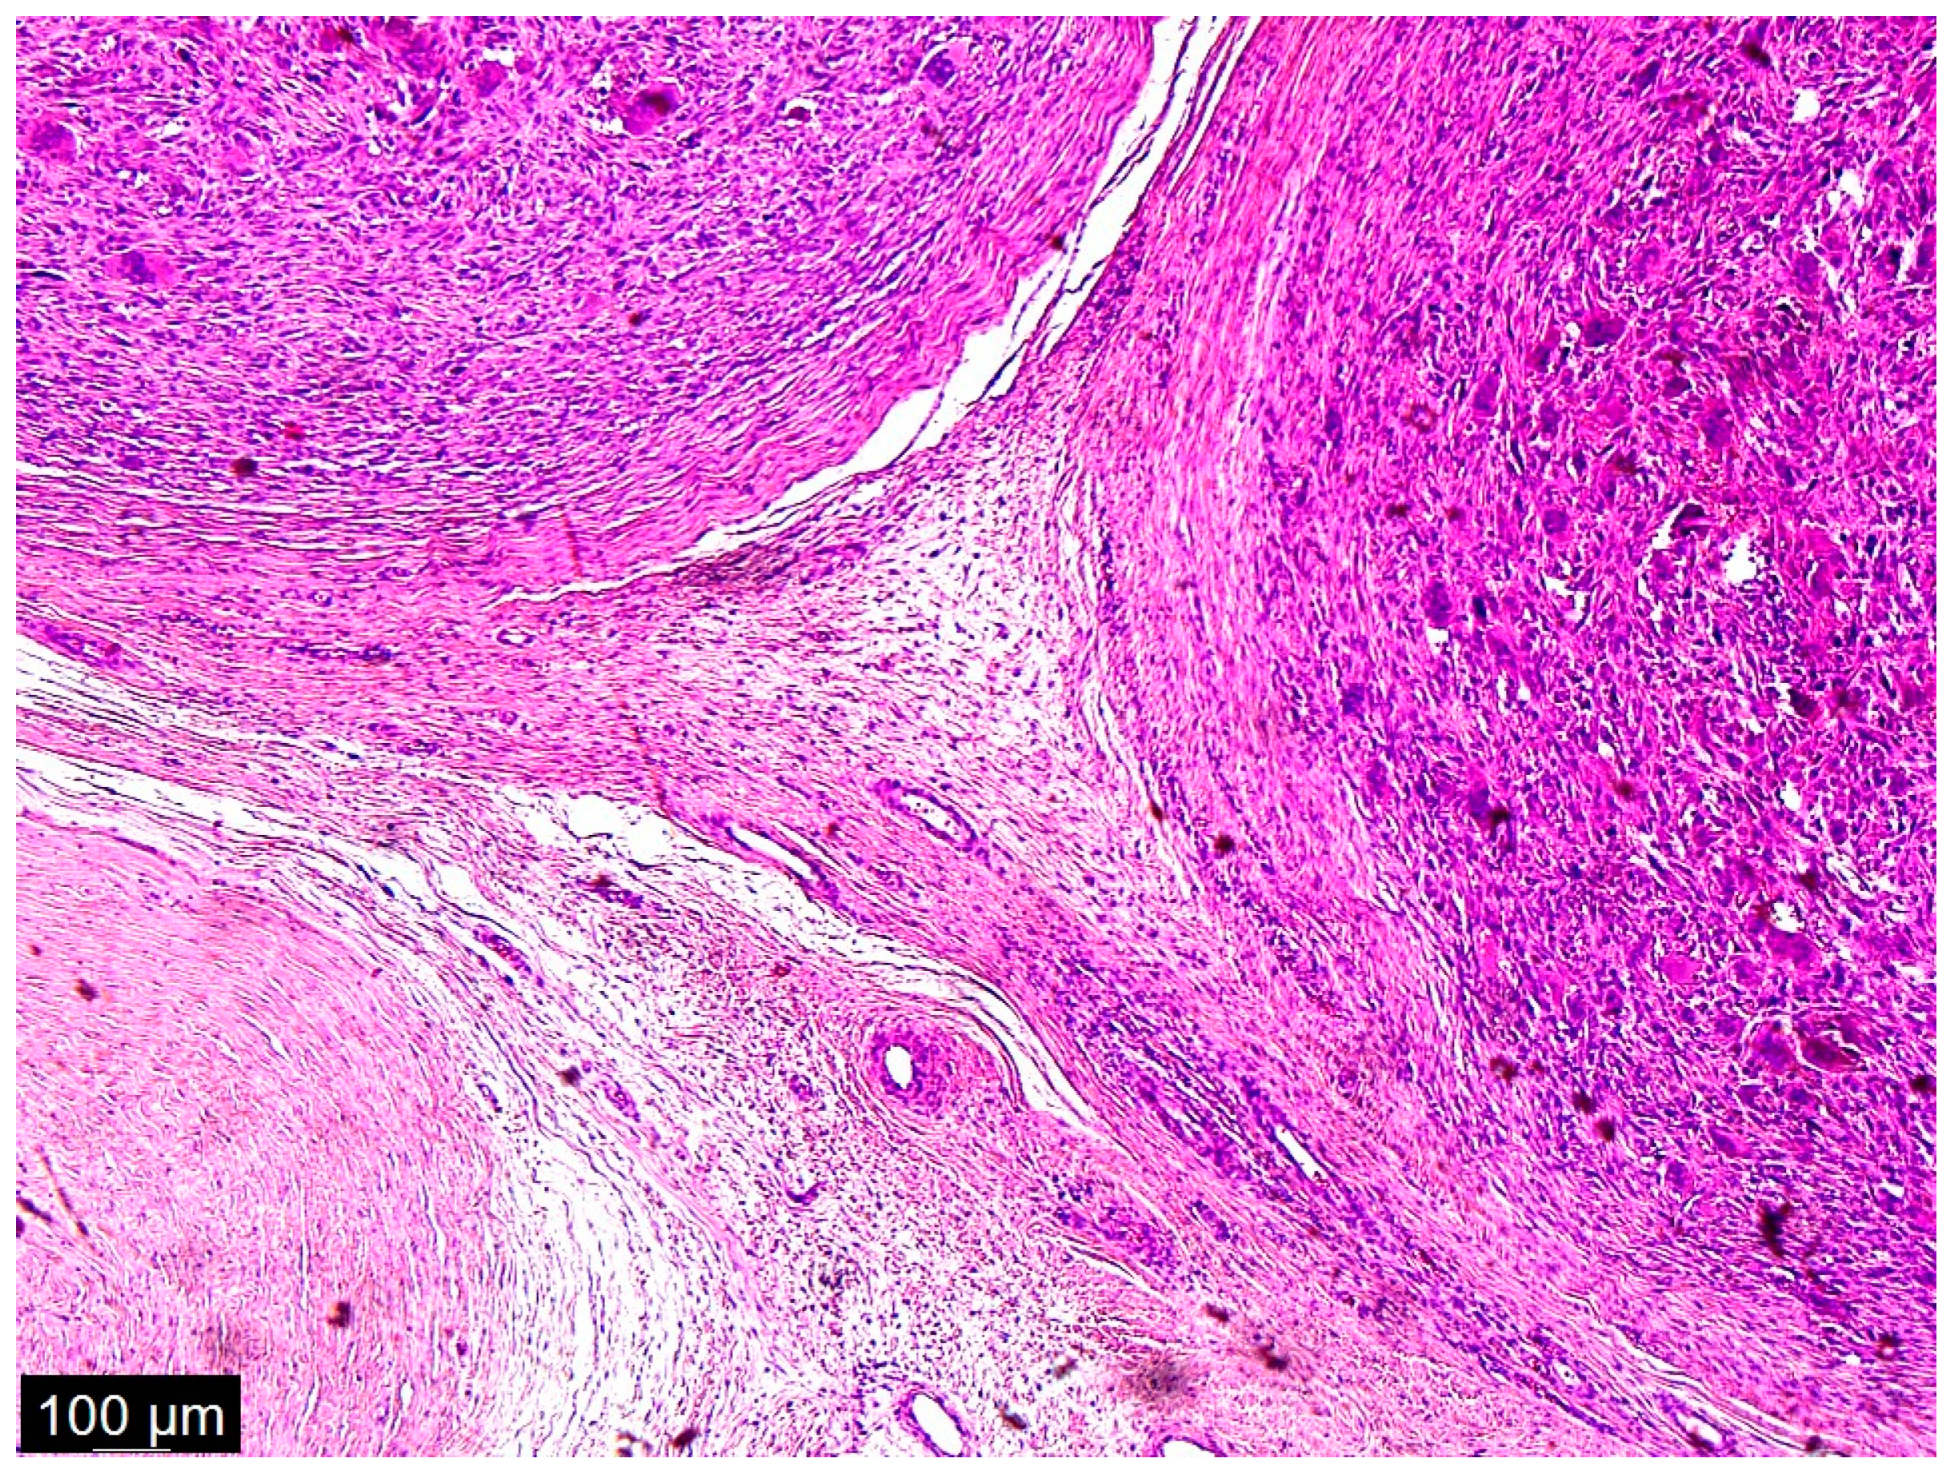

Figure 4.

A low magnification of the tumor showed a nodular mass. The nodules were formed from multinucleated giant cells and mononuclear cells. Interspersed among these structures were spindle cells, some of which were pleomorphic and some of which were simply dark and hyperchromatic. This was not a typical case, because in the textbook definition of dedifferentiated liposarcoma, there are parts of well-differentiated liposarcoma and atypical squamous cells which we did not see in this case; there were just scattered spindle cells and a heterologous component.